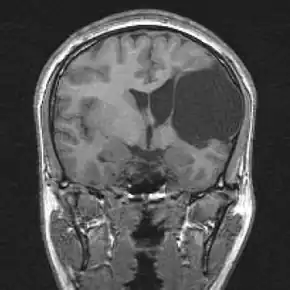

| Porencephalic cyst in the left parietooccipital and right frontal area.[1] | |